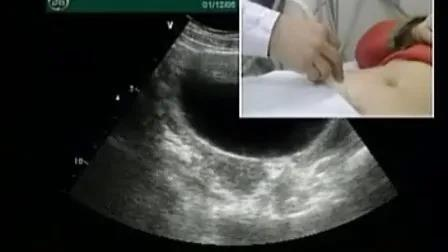

顾名思义,经腹部就是需要检查者饮水使膀胱充盈(既憋尿),通过充盈的膀胱作为透声窗来观察子宫和附件的情况,检查时取仰卧位,暴露下腹部,检查区涂抹耦合剂,其图像质量取决于腹壁厚度及膀胱充盈度。

经腹部超声扫描范围比较广,对于较大的子宫肌瘤、附件区肿块等占位性病变,能更加清晰地显示病变的形态、轮廓及与邻近组织的关系,而经阴道超声因声窗和穿透性受限,经常无法清晰显示较大肿块的全貌。

经阴道就是排空膀胱,取膀胱截石位,在阴式探头上面套上安全套,将探头轻柔放入阴道内,旋转探头调整角度以获得满意切面,来观察子宫和附件的情况。